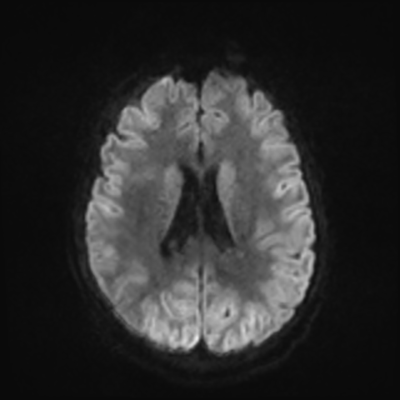

MRI brain (DWI)

MRI brain (DWI) 3/24 3/24

You can clearly see diffuse cortical and basal ganglia diffusion restriction, and that of his deep cerebellar nuclei as well. The right occipital lobe abnormalities are a little more prominent, but then you remember that he is known to have had a right occipital stroke weeks ago.

In reviewing his data, you know that he doesn't have any of the strong predictors of a poor neurologic prognosis. However, based on these findings on MRI, along with the absent reactivity on cEEG, you are able to tell the primary team and the patient's family that he is likely to have a poor prognosis, based on these multiple moderate predictors. Recovery is not completely impossible-- there is more uncertainty with this prognostication than if we were able to get SSEPs-- but you're very worried about his outlook and that any potential recovery would require a very protracted rehabilitation period. Given his high cervical cord injury level, tracheostomy would be required anyway. So, it comes down to whether his family thinks he'd want to pursue these aggressive measures.